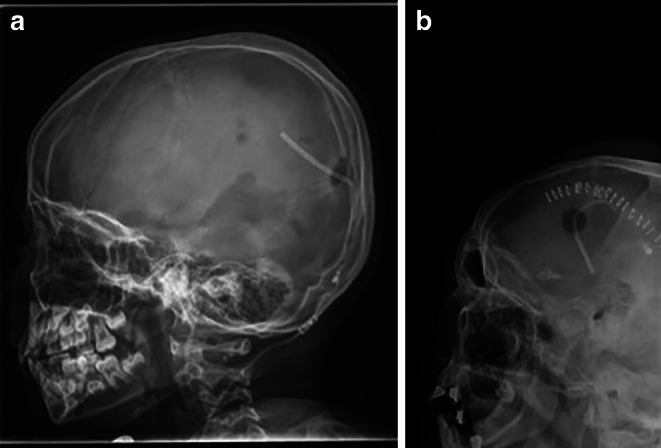

Introduction: Ventriculoperitoneal shunts (VPS) are an essential part of the treatment of hydrocephalus, with numerous valve models available with different ways of indicating pressure levels. The model types often need to be identified on X‑rays to assess pressure levels using a matching template. Artificial intelligence (AI), in particular deep learning, is ideally suited to automate repetitive tasks such as identifying different VPS valve models. The aim of this work was to investigate whether AI, in particular deep learning, allows the identification of VPS models in cranial X‑rays.

Methods: 959 cranial X‑rays of patients with a VPS were included and reviewed for image quality and complete visualization of VPS valves. The images included four VPS model types: Codman Hakim (n = 774, 81%), Codman Certas Plus (n = 117, 12%), Sophysa Sophy Mini SM8 (n = 35, 4%) and proGAV 2.0 (n = 33, 3%). A Convolutional Neural Network (CNN) was trained using stratified five-fold cross-validation to classify the four VPS model types in the dataset. A finetuned CNN pretrained on the ImageNet dataset as well as a model trained from scratch were compared. The averaged performance and uncertainty metrics were evaluated across the cross-validation splits.